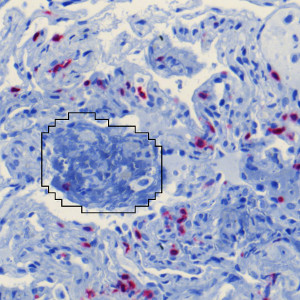

Figure 3

Close up of lung tissue, with CD3 stained areas (red).